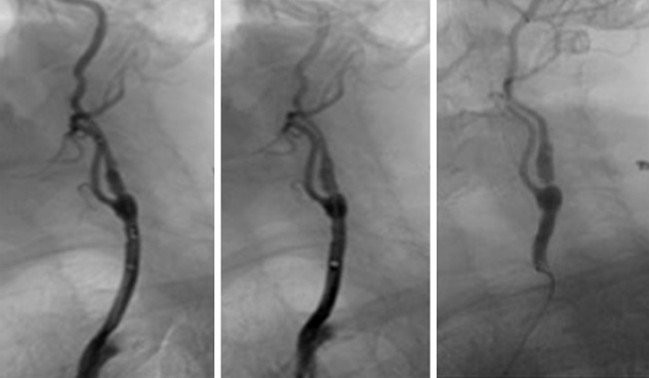

(3)頸椎內外血管扭曲:

抬頭、擺動頭頸部或長期姿勢不良等,導致頸椎內外血管流動不暢順,影響血液來往腦區域,導致頭暈、頭痛。

Image source: Vascular Care Centre – “Carotid Arteries”

https://vascularcarecentre.com/for-patients/conditions/arterial-disease/carotid-arteries/